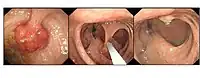

Therapeutic endoscopy is the medical term for an endoscopic procedure during which treatment is carried out via the endoscope. This contrasts with diagnostic endoscopy, where the aim of the procedure is purely to visualize a part of the gastrointestinal, respiratory or urinary tract in order to aid diagnosis. In practice, a procedure which starts as a diagnostic endoscopy may become a therapeutic endoscopy depending on the findings, such as in cases of upper gastrointestinal bleeding, or the finding of polyps during colonoscopy.

A number of different techniques have been developed to allow treatment to be carried out endoscopically, to treat disorders such as bleeding, strictures and polyps.